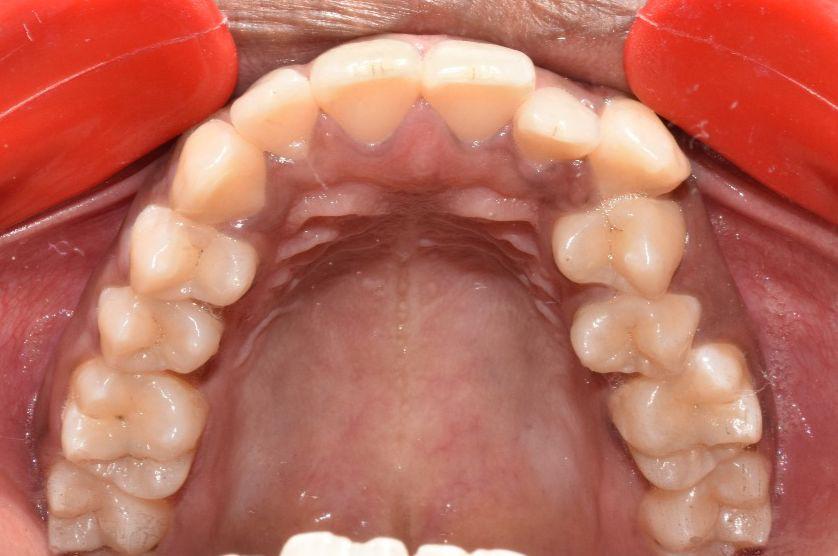

Before & After Results

At Aline Dent, we take pride in delivering visible and lasting improvements in our patients’ smiles. Our before-and-after results highlight the effectiveness of modern dental treatments combined with personalized care. This gallery showcases real dental cases treated at our clinic, giving you a clear idea of how different dental concerns can be corrected with the right treatment approach.

From minor corrections to complete smile enhancements, these teeth transformation results demonstrate how professional dental care can improve both oral health and appearance. Our experienced dental team carefully evaluates each patient’s needs and creates customized treatment plans to achieve natural, healthy, and confident smiles.

In this gallery, you will find a variety of smile makeover cases, including treatments for crooked teeth, gaps, discoloration, damaged teeth, and other common dental concerns.